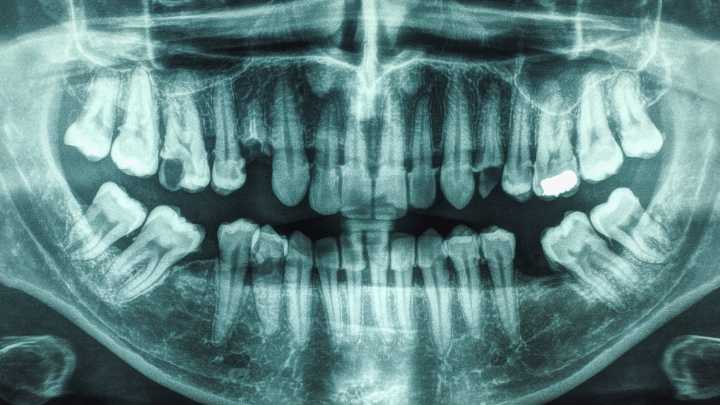

Oral hygiene has been linked to multiple health conditions, including dementia and diabetes . Now, research shows that people with both gum disease and more tooth cavities also have a notably higher risk of stroke.

Both have been individually associated with stroke in the past, but few studies have analyzed the conditions in combination. So a study led by a team from the University of South Carolina restricted their investigation to individuals with cases of periodontal disease and dental caries.

"We found that people with both cavities and gum disease had almost twice the risk of stroke when compared to people with good oral health, even after controlling for cardiovascular risk factors," says Souvik Sen, the chair of the neurology department at the University of South Carolina.